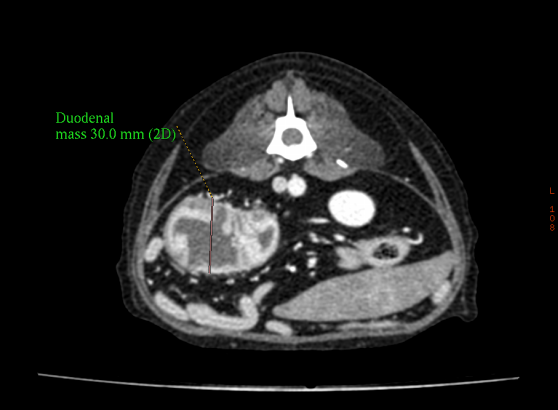

CT 촬영

단시간의 촬용으로 정밀한 3D입체영상을 얻을 수 있습니다.

신체검사

미세침흡인세포검사

미세한 주사바늘로 소량의 세포를 얻은 후 양성 혹은 악성의 세포 진단을 목적으로 시행합니다.